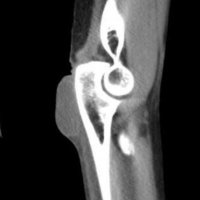

Olecranon bursitis refers to inflammation of the olecranon bursa. The olecranon bursa is a subcutaneous space lined with a synovial membrane that secretes fluid to provide smooth and almost frictionless motion between the skin, the subcutaneous tissues, and the olecranon. Because of its superficial location, it is a common site for injury, inflammation, and infection. Repeated traumatization of the elbows at work led to common terms for different forms of occupational bursitis such as “student's elbow” or “miner's elbow”.

Lateral radiograph of the elbow reveals soft tissue swelling superficial to the olecranon. Ultrasound may show a fluid collection in the olecranon bursa, features of synovial proliferation and/or hyperemia.

CT will show fluid density at the subcutaneous tissue superficial to the elbow. Bursal fluid collection in MRI has the following features: hypointense-T1, mainly hyperintense-T2, and enhancement of bursal margins in post contrast imaging.